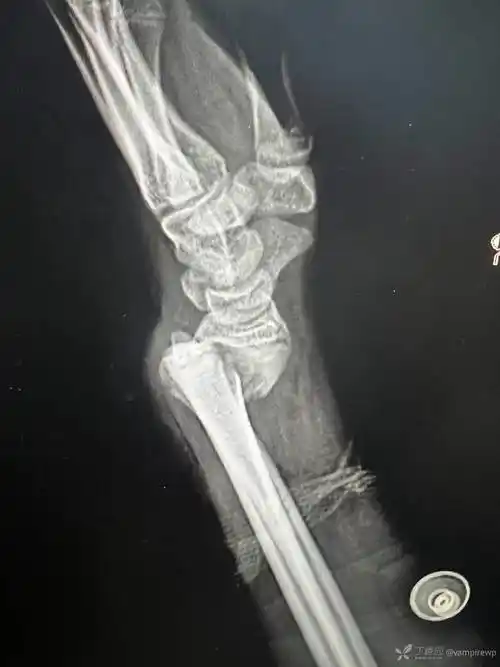

桡骨远端骨折史密斯